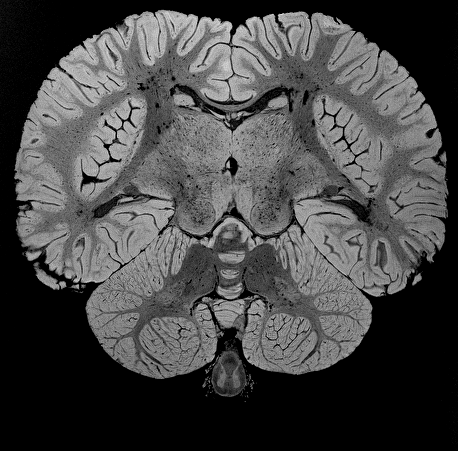

The Brain Catalogue: An open portal for comparative neuroanatomy researchThe Brain Catalogue is a project to create an open-access catalogue of high-quality vertebrate brain MRI.

We are currently scanning and processing the collection of vertebrate brains from the Muséum National d'Histoire Naturelle de Paris, and building online tools to visualise and analyse the data, collaboratively.